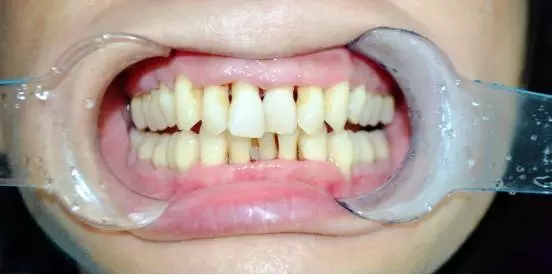

一周后陸小姐復(fù)診,

牙齦出血有好轉(zhuǎn),但患牙仍有松動(dòng),能夠發(fā)現(xiàn),齦乳頭萎縮,醫(yī)生繼續(xù)采用階段性牙周治療,慢慢讓牙齦紅腫消除,繼續(xù)常規(guī)消毒,齦下刮治,沖洗,上藥?;颊咝枰龊萌粘5目谇蛔o(hù)理。

半個(gè)月后

檢查:牙齒松動(dòng)度緩解,牙齦邊緣無紅腫,無明顯探診出血